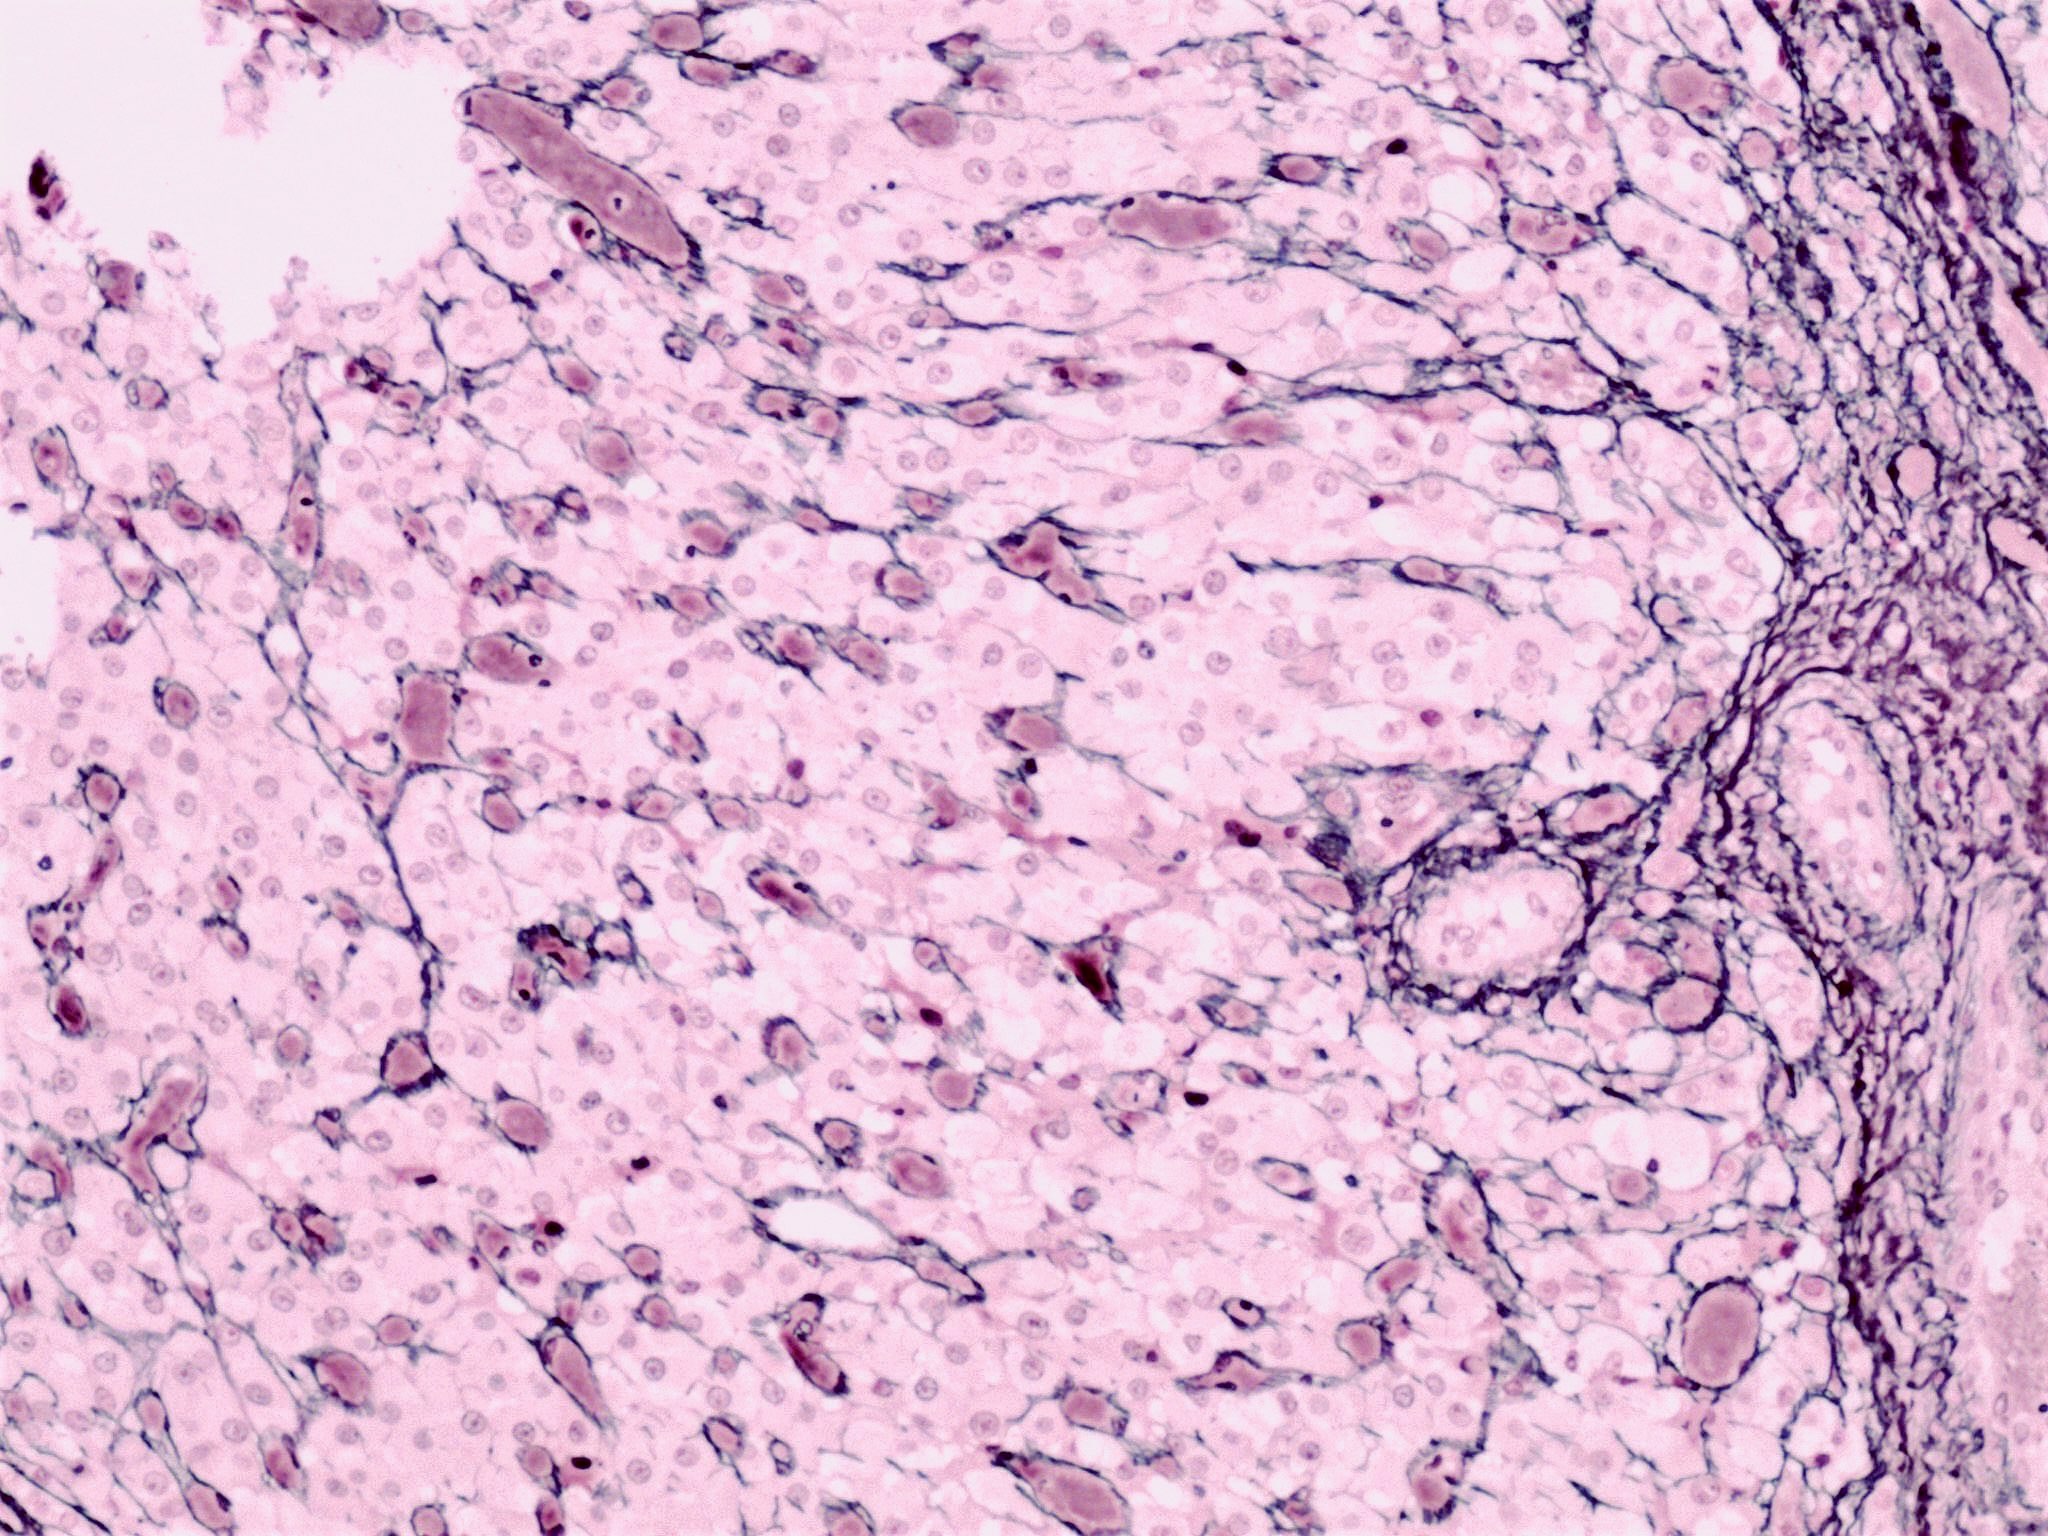

Microscopic (histologic) description

- Cyst lining is convoluted, composed of an inner layer of luteinized granulosa cells and outer layer of theca cells

- Granulosa cells are polygonal in shape, with abundant eosinophilic cytoplasm and central round nuclei

- Mitotic figures may be seen in the granulosa cells

- Outer theca cells are smaller in size

- Prominent inner layer of fibrous tissue

- Reference: Kurman: Blaustein's Pathology of the Female Genital Tract, 7th Edition, 2019

Microscopic (histologic) images

Positive stains

- Usually not necessary for diagnosis

- Calretinin (Histopathology 2001;38:403)

- Inhibin (J Clin Endocrinol Metab 1991;73:470)

- Progesterone receptor (Reproduction 2004;128:423)

- Reticulin preserved within the theca interna layer

- Reticulin diminished / absent in the granulosa layer